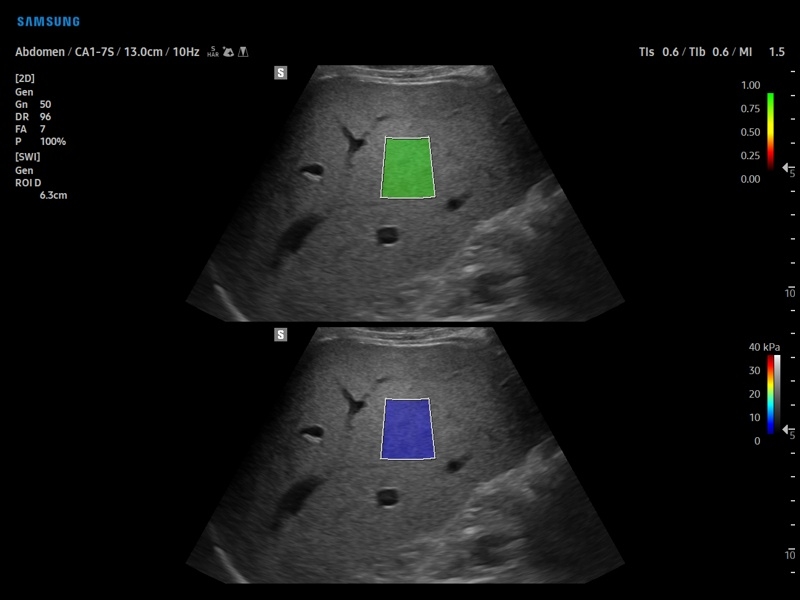

• S-Shearwave Imaging для эластографии сдвиговой волной

Эластография сдвиговой волной/Эластометрия:

• Модуль S-Shearwave imaging – программа цветовой сдвиговой эластографии позволяющая автоматически определять индекс жесткости различных участков исследуемого объекта в кПа или м/с, получая при это еще и индекс достоверности данных RMI.